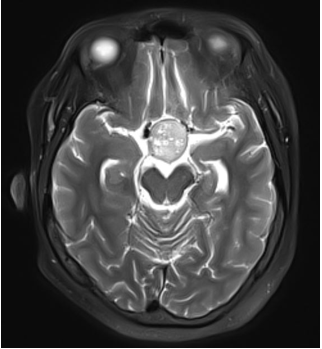

T2像提示肿瘤质地不均